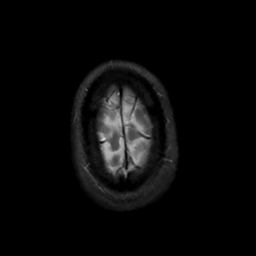

MR Study #7, March 24, 1991 -- Slice #46